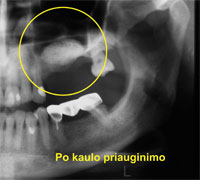

Sinus Augmentations: One of the most frequently applied grafting procedures is the Sinus Augmentation. This procedure is restricted only to the upper jaw. As we get older our sinuses grow larger in volume and literally take away valuable bone from the jaw ridge. This is not a pathological condition, on the very contrary, it happens to almost every one. This process is called Pneumatization of the Para-nasal sinuses.

Once teeth are lost in that particular area it makes it difficult if not impossible to place endosseous implants in that area. For this particular problem a grafting method was developed to literally raise the bottom of the sinus back up, graft bone underneath and, thus, create enough space for one or more dental implants. Sinus Augmentations and implant placement can sometimes be performed as a single procedure, if enough bone between the upper jaw ridge and the bottom of the sinus is available to stabilize the implant well. If not enough bone is available, the Sinus Augmentation will have to be performed first, then the graft will have to mature for several months (depending on the graft material used). Once the graft has matured the implants can be placed. |